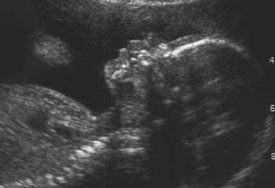

Your baby is especially at risk in the first few weeks of pregnancy. Having just one x-ray on a body part away from the. The concern about X-rays has to do with the possible effects of radiation on fetal development.

What if Ive had multiple x-rays while pregnant. X-ray exposure in very early pregnancy can result in decreased fetal growth but only if the fetus is exposed to 5 to 50 rads or more CDC reports. Because the embryo is made up of only a few cells.

Extensive x-ray exposure during pregnancy can adversely affect the foetus inside her uterus. Risks of an x-ray at 4 weeks pregnant. But the risk is very.

40-240 millirad for an x-ray of the pelvis. The development of the brain of the foetus may be affected which can damage the. At present it is not known for sure if the small amounts of.

The crucial and vulnerable part of pregnancy in x-ray exposure is at the 8th to 15th gestation weeks. Answer 1 of 3. They can be used on their own or as part of a different radiology test like a computed.